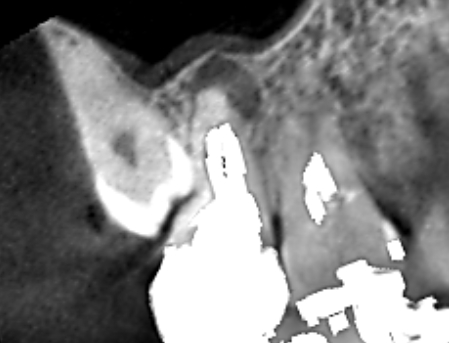

上顎第二大臼歯の矢状断のCT画像です。

赤い矢印の先に膿の影がみられます。